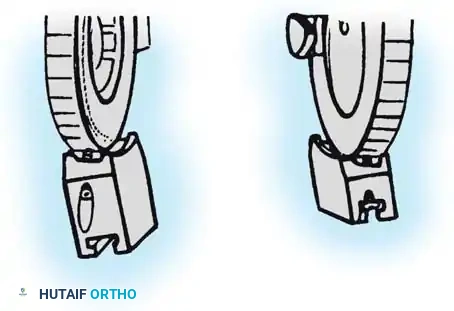

Fig. 58-27 Design features of the hinged elbow external fixator, noting the built-in 7 degrees of valgus to approximate the distal humerus anatomy.

Preoperative assembly is vital. The hinge block must be configured so the large block sits medially. The differential block height accommodates the average 7 degrees of distal humeral valgus, ensuring the upper ring remains perpendicular to the humerus while the axis of rotation is perfectly aligned.

The Compass hinge arrives assembled for a right arm.

Fig. 58-28A The Compass hinge in its default right arm configuration.

To convert it for a left arm, remove the proximal 5/8-inch ring by loosening the T-bolts. Remove the proximal blocks using a 9/64-inch hex wrench.

Fig. 58-28B Switch the blocks to the opposite wheel, rotating each block 180 degrees so the tilt is reversed.

Resecure the blocks tightly and replace the proximal ring.